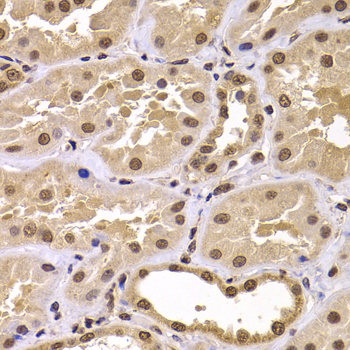

Immunohistochemistry of paraffin-embedded human kidney using CSRP2BP antibody at dilution of 1:100 (x400 lens).